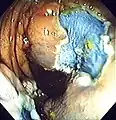

Polyp is identified.

A sterile solution is injected under the polyp to lift it away from deeper tissues.

A portion of the polyp is now removed.

The polyp is fully removed.